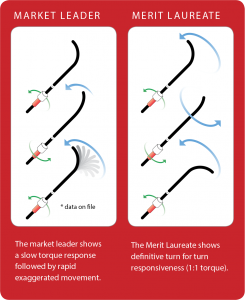

Designed to provide true 1:1 torque response to facilitate navigation and rapid vessel selection.

Merit Laureate hydrophilic guide wires facilitate the placement of devices during diagnostic and interventional procedures. Its exceptional torque control, turn-for-turn responsiveness, and enhanced lesion crossability demonstrates high performance in navigating tortuous vessels. The hydrophilic coating demonstrates enduring lubricity and consistent surface coating adhesion. The Laureate was designed to reduce wire whipping, minimize friction, and to promote rapid catheter exchanges.

Comparative torque testing showed the Merit Laureate guide wire consistently met the 1:1 torque target.